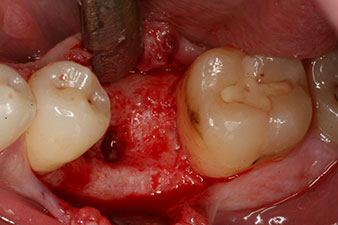

Sechs Wochen nach Extraktion zeigte sich jedoch nach Präparation des Mukoperiostlappens im Bereich der ehemaligen mesialen Alveole eine unvollständige Ossifikation.

Nach gründlicher Entfernung des Granulationsgewebes wurde das Implantat wie geplant eingebracht (blueSky, bredent).

Wegen des unzureichenden Knochens krestal am Implantat wurde der Bereich mit den bei der Präparation des Implantatlagers gesammelten Knochenspänen augmentiert und speicheldicht vernäht.